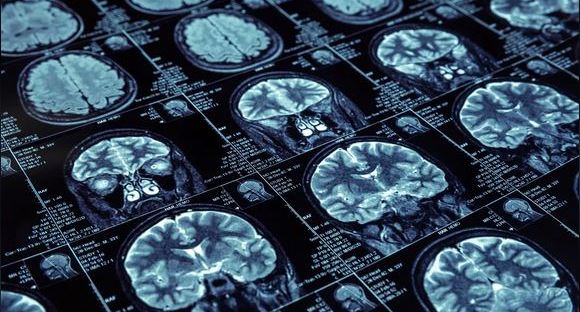

A stroke takes place when the blood supply to the brain is cut off, either totally or partially. Because brain cells require oxygen and nutrients constantly, if the blood supply is not restored on time, the cells will start dying. This is why it is extremely important to get the patient to receive treatment as soon as you suspect stroke symptoms. The following are some tell-tale signs of a stroke: loss of movement, feeling, and/or vision on one side of the body, combined with dizziness, confusion, and difficulty in speaking. People who smoke, have high blood pressure or cholesterol, diabetes, and obesity are at a higher risk of suffering from a stroke. You can prevent a stroke from happening by quitting tobacco consumption, eating or drinking healthy, exercising, and taking good care of your heart.